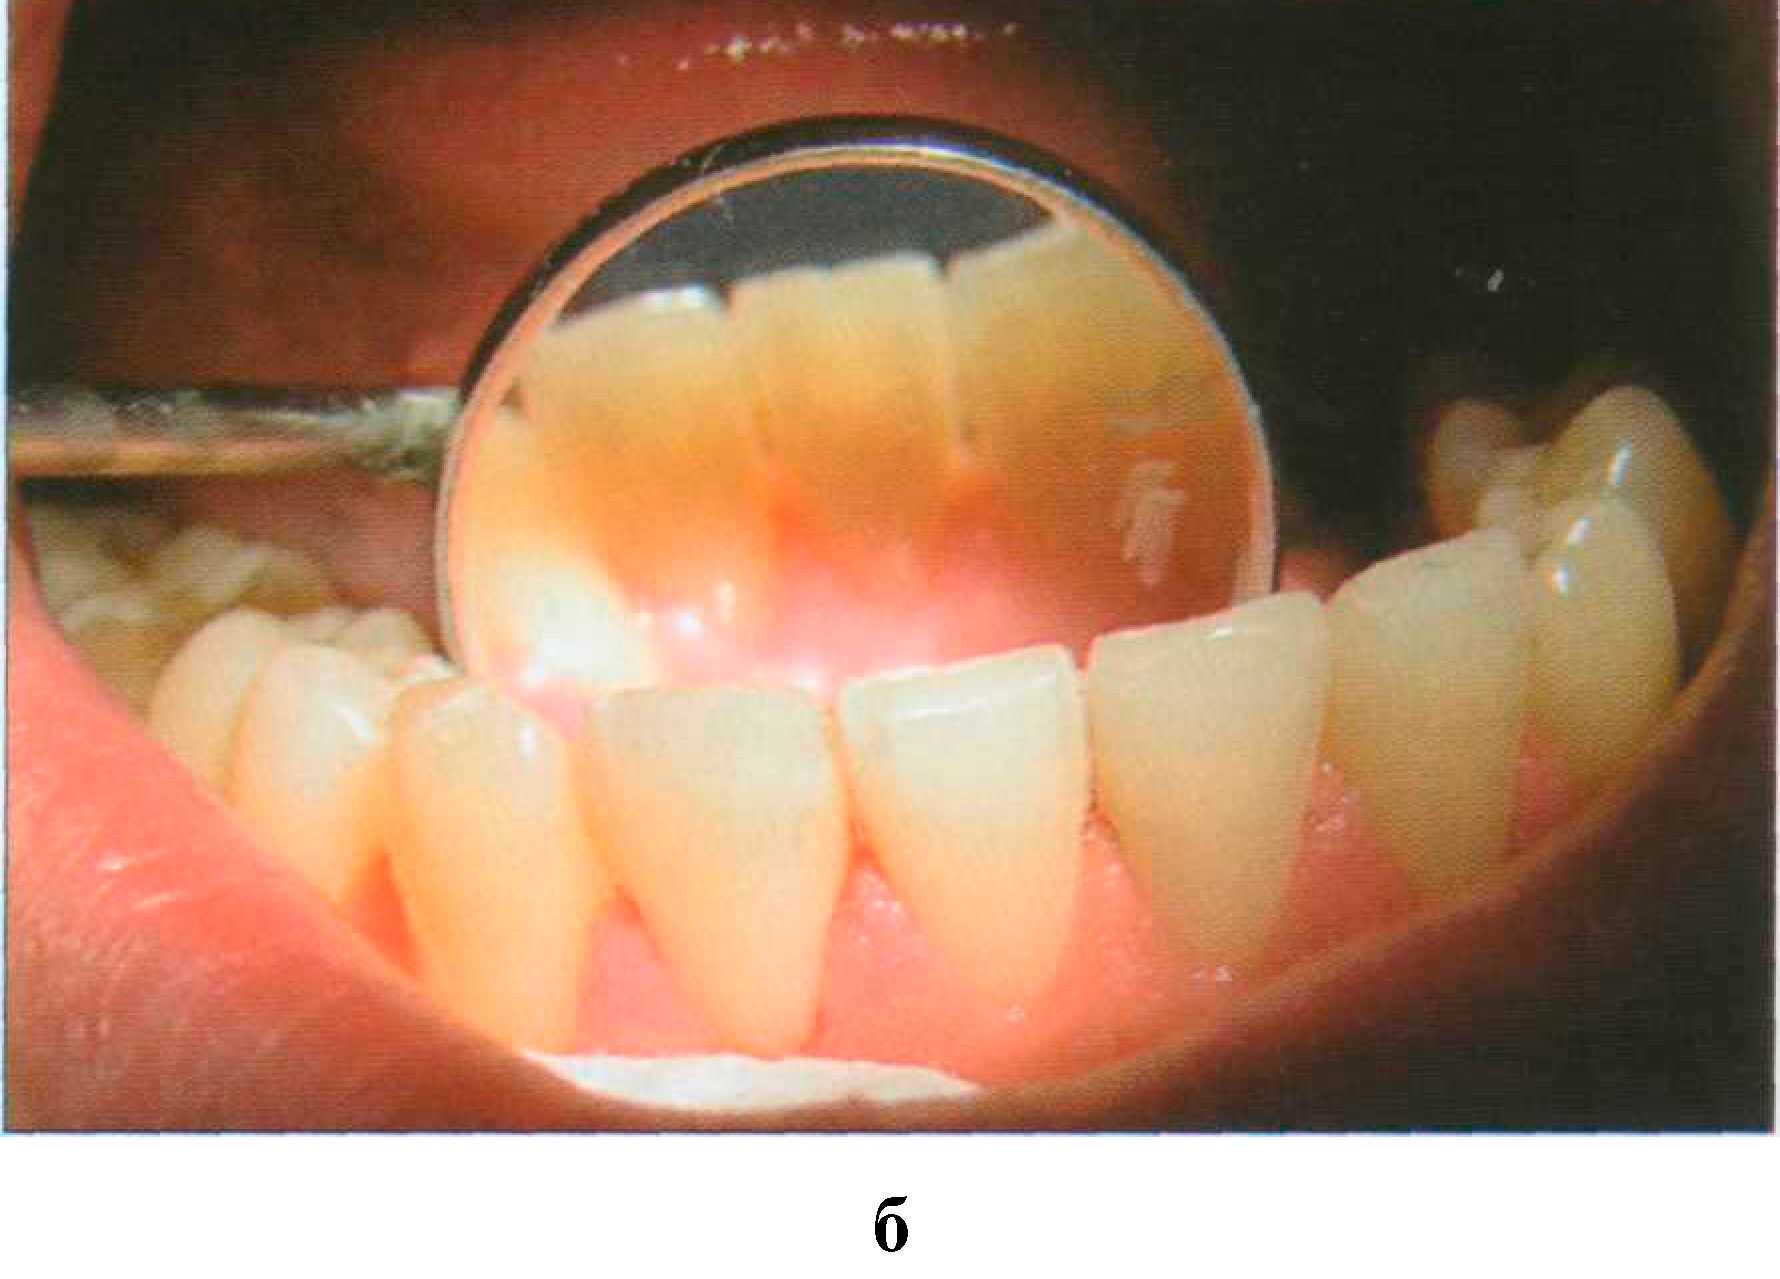

Благодаря высокой пористости участки деминерализации могут пигментироваться, приобретая желтоватую, бурую, коричневую окраску в зависимости от воздействующего красителя. Пары брома и йода окрашивают пришеечные области зубов в желтоватый цвет. Коричнево-черный налет на зубах появляется у лиц, занятых обработкой металлов (марганец, железо, никель). Хроническое отравление ртутью, сулемой, свинцом приводит к диффузному окрашиванию зубов различной интенсивности от серого до черного или от желтого до коричневого цвета. Особо следует остановиться на пигментации зубов у курильщиков (экзогенное, системное, поверхностное и глубокое окрашивание). Наиболее характерно образование темно-коричневого, почти черного налета вдоль шеек зубов, а также на тех поверхностях, которые не участвуют в жевании и плохо очищаются. Образованию «налета курильщиков» способствует плохая гигиена полости рта (рис. 173 а, б).

Рис. 173. Выраженная пигментация язычной поверхности резцов: налет "курильщика" — а; состояние после профессиональной гигиены — 6 Сходная окраска, которую можно отнести к воздействию пищевых пигментов, однако менее интенсивная и менее стойкая, чем у курильщиков, наблюдается у любителей крепкого чая и кофе. Содержание в питьевой воде железа может вызвать устойчивую синеватую окраску зубов. Выраженная пигментация органических покровов зуба может появляться в результате воздействия хлоргексидина, который назначают для полосканий (рис. 174).